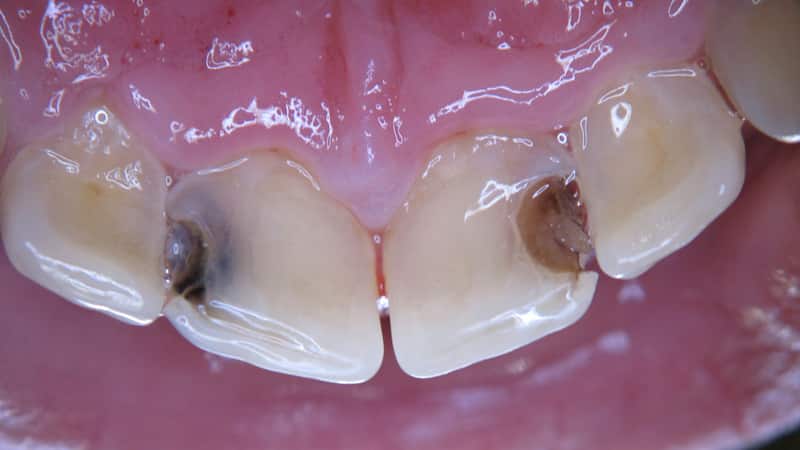

Стадия пятна (macula cariosa). Эмаль теряет свой естественный блеск из-за деминерализации. На боковых поверхностях передних резцов появляются мелкие матовые пятна, которые могут варьироваться от белых до темно-коричневых. Структура эмали начинает разрушаться, так как зубные ткани теряют кальций и другие минералы. Если вовремя начать лечение и улучшить гигиену полости рта, процесс можно замедлить и стабилизировать, а пятно исчезнет. В противном случае деминерализация прогрессирует, и пятно переходит в поверхностный кариес.

Поверхностный кариес (caries superficialis). Первым признаком является появление боли при контакте пятна с холодной, горячей, сладкой или кислой пищей. На этой стадии стоматолог может уже выявить кариозную полость, и существует риск поражения дентина.

Глубокий кариес (caries profunda). На этой стадии дентин размягчается и заполняет образовавшуюся кариозную полость. Пациенты жалуются на сильные боли при воздействии температурных и химических раздражителей. Также может возникать ноющая боль при зондировании дна полости. Иногда появляются признаки пульпита.